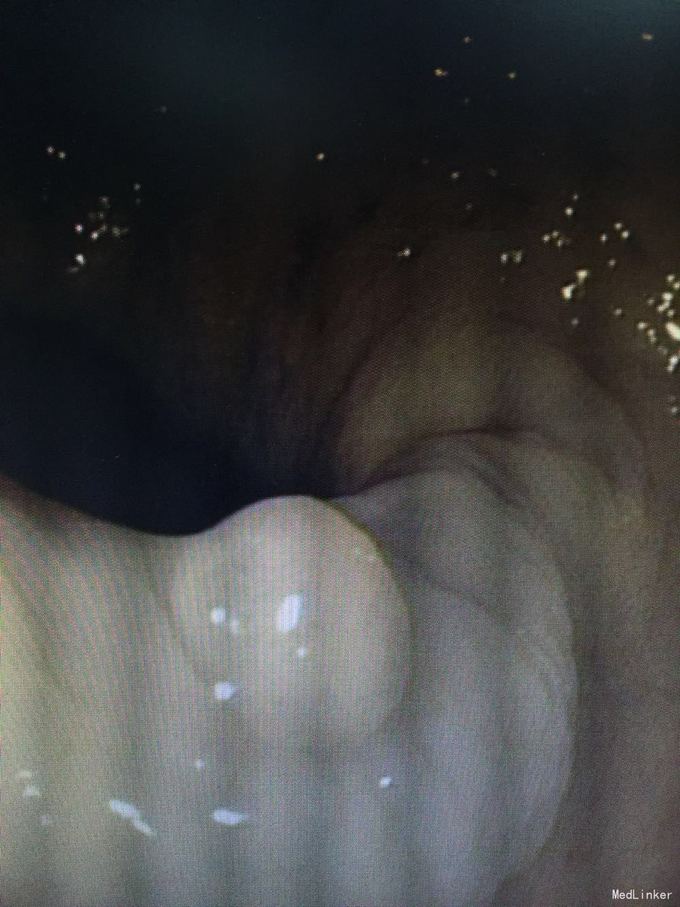

查体:左侧小腿肌肉轻度萎缩,余无特殊。辅助检查:三大常规、生化、类风湿四项、体液免疫、ANCA四项均未见异常。癌胚抗原稍升高,7.5ug/l。肌电图:双侧正中神经周围神经源性损害(感觉纤维受累)。胸片:右肺尖结节影,考虑钙化灶。复查CK逐渐降低。鼻咽镜示慢性鼻炎。胃镜示慢性浅表性胃炎。肠镜示肠息肉。腹部彩超:肝内胆管轻度扩张,大便肝吸虫卵计数200个/克。肌肉活检提示送检横纹肌组织有灶性变性,间质有极少量的淋巴细胞浸润。动态血压提示高血压。